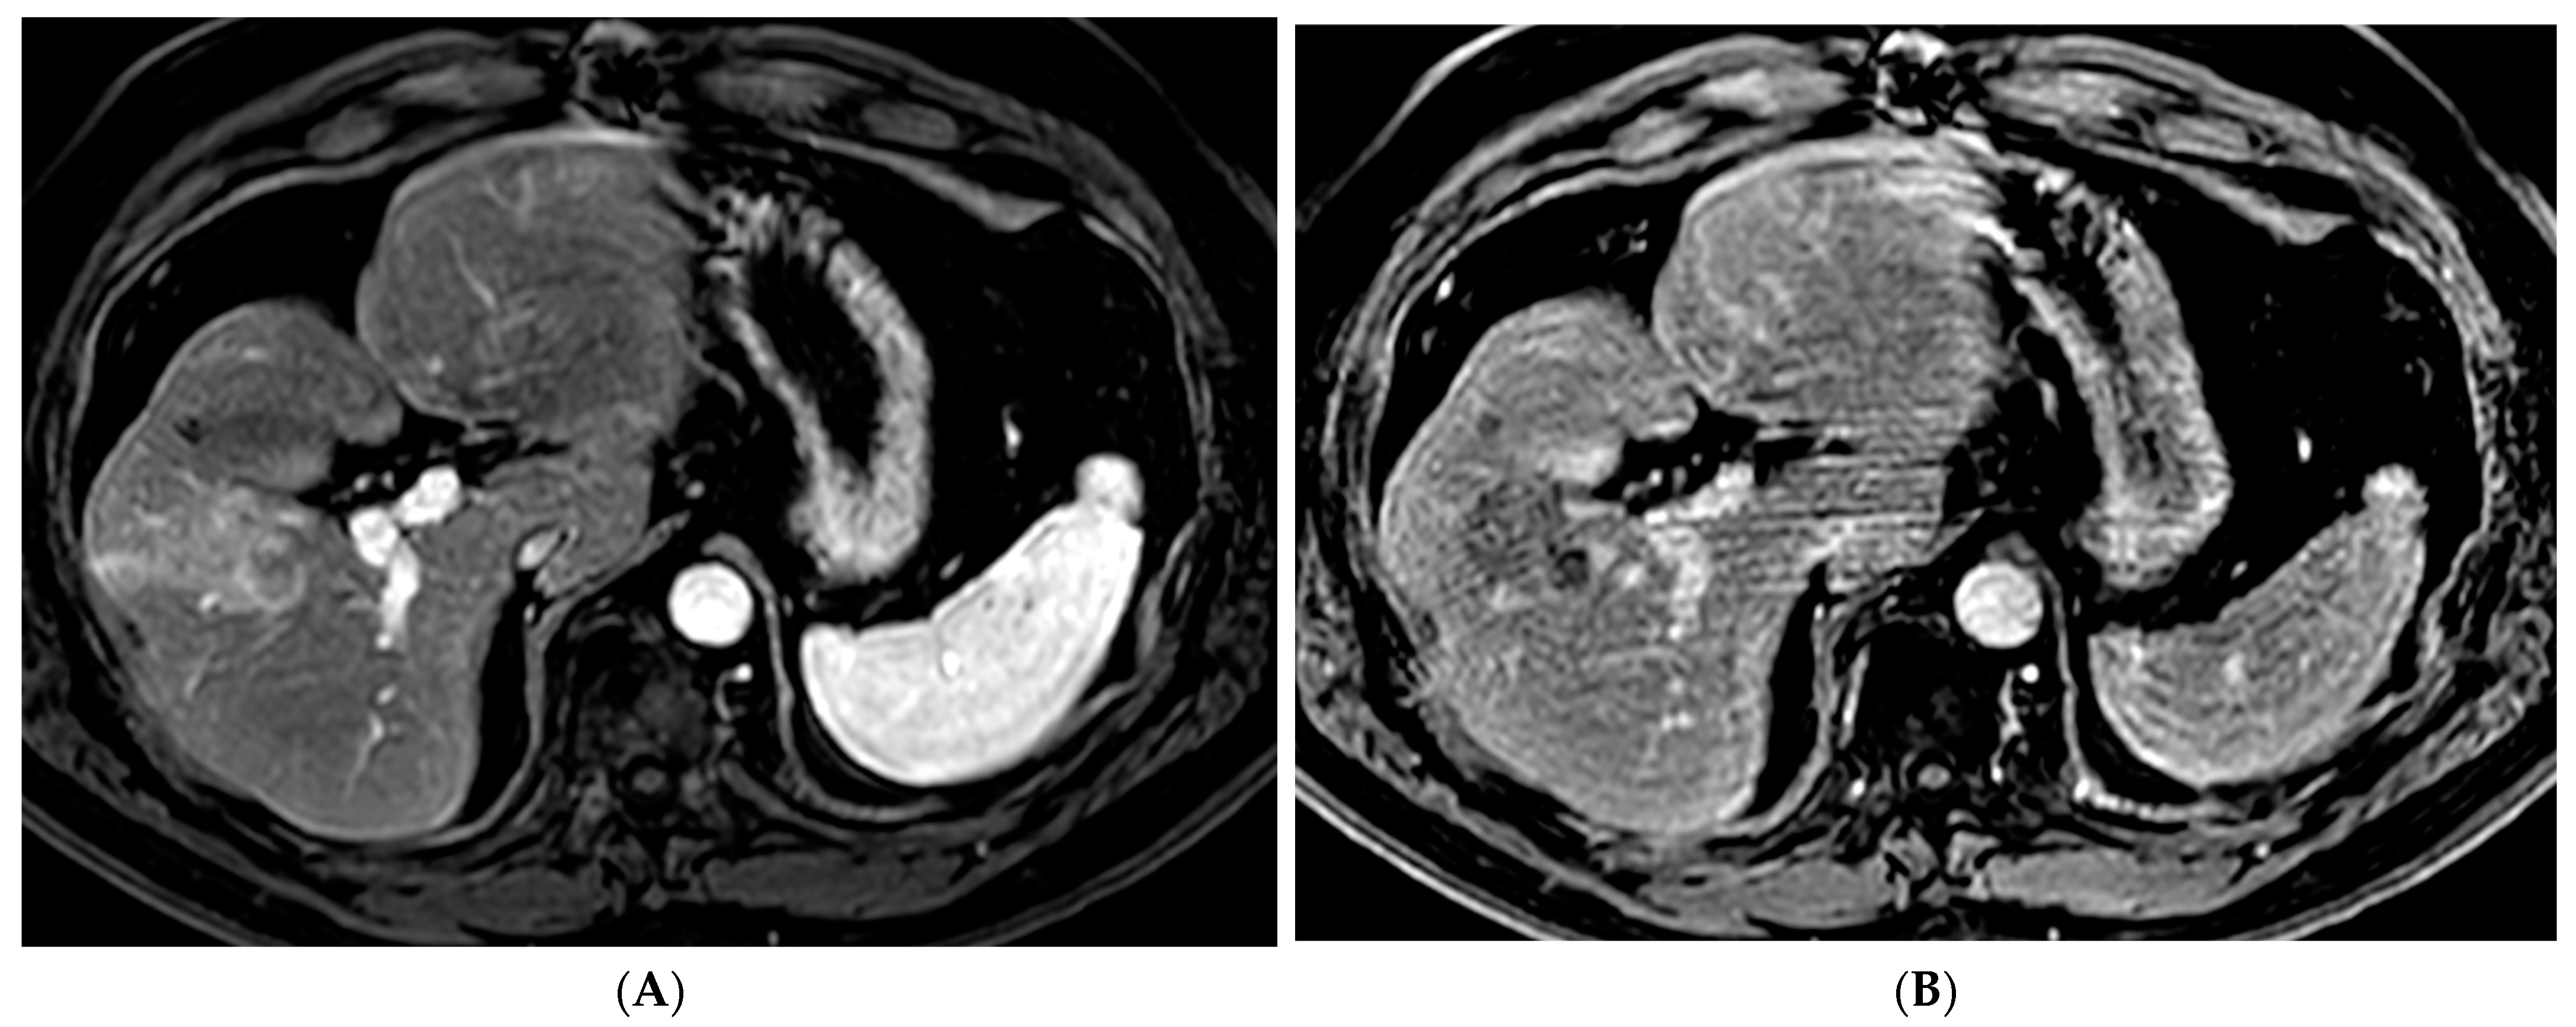

Figure 4. 72-year-old man with HCV cirrhosis and HCC treated with combined cTACE and cryoablation as a bridge to transplant. (A) Arterial phase MRI demonstrates a 2.2 cm segment 4a hypervascular lesion. (B) Digital subtraction angiography images during cTACE procedure demonstrate that the tumor was supplied by both the segment 4a branch vessel (image shown) and segment 2 artery (not shown). cTACE was performed using doxorubicin 50 mg, cisplatin 100 mg, and mitomycin 10 mg followed by PVA 150–250 micron particles. (C) A non-contrast CT scan performed on post-operative day 1 demonstrates a heterogeneous uptake of ethiodized oil within the tumor. Cryoablation was then performed using two probes. Coronal and axial CT images from the procedure demonstrate the probes adjacent to the ethiodized oil staining (D) and the ice ball (E). (F) A follow up contrast enhanced MRI in the arterial phase demonstrates no residual viable tumor.

The combination of locoregional therapies is also an area of interest. In a meta-analysis, the combination of TACE and RFA compared to surgical resection showed no difference in overall survival but reduced complications in the combination therapy group [65]. The ethiodized oil retention within HCC following cTACE can also be used as a marker to guide percutaneous ablation (Figure 4). Stereotactic body radiotherapy (SBRT) is currently being studied in combination with TACE with promising results. In a propensity-scored matched analysis by Wong et al., patients who received the combination of SBRT + TACE had significantly higher one- and three-year overall survival and improved radiological disease control [66]. There is also interest in using SBRT in cases of local relapse following TACE. A phase III trial was closed early due to slow accrual, but results showed superior local control of SBRT versus repeat TAE/TACE [67]. SBRT remains a promising non-invasive treatment for unresectable HCC. Further research is needed to define its role within the HCC treatment paradigm.